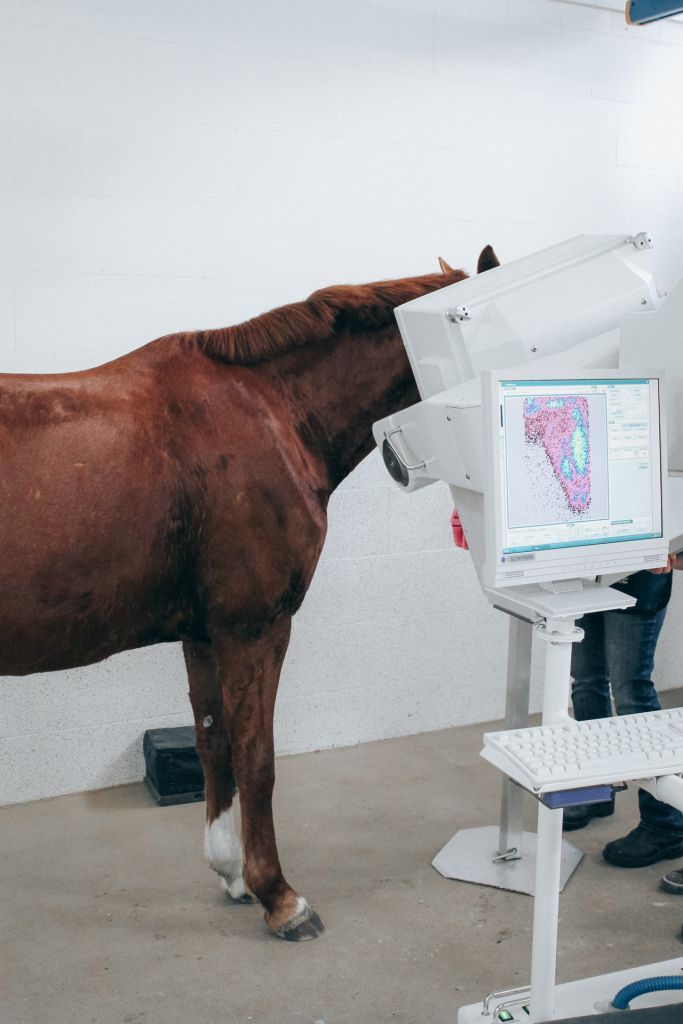

Scintigraphy on a Standing Horse

An ingenious combination of mechanics, electronics, and software makes scintigraphy on a standing horse easily achievable. Experience gained from human medicine, including detector specifications, measurement methods, and processing, as well as feedback from our many customers, has enabled us to achieve the goal of easy and fast diagnosis.

To minimize motion artifacts for the standing horse, MiE has developed the world’s first real-time motion correction. The rigid registration software allows shorter image acquisition times and improved diagnostic quality. Using the ParalyzerPLUS software eliminates the need to repeat acquisitions.

MiE’s Image Fusion for scintigraphy and x-ray images enhances the diagnostic possibilities. The program evaluates the different structures, resolution, acquisition geometries and regions. Rotation, translation (shift) and scaling will be adjusted.

The process operates multi modal and automatic. The fusion allows the combined usage of the morphologic information of the x-ray and the functional information of the scintigraphy in one image.